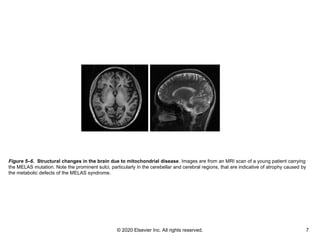

Figure 5–6. Structural changes in the brain due to mitochondrial disease. Images are from an MRI scan of a young patient carrying

the MELAS mutation. Note the prominent sulci, particularly in the cerebellar and cerebral regions, that are indicative of atrophy caused by

the metabolic defects of the MELAS syndrome.